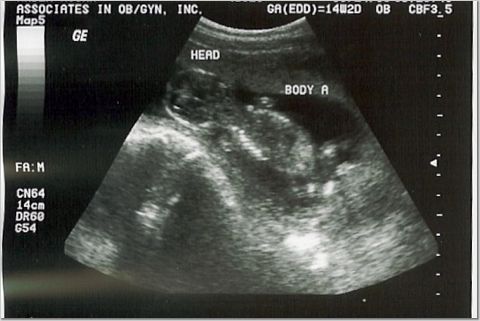

14 weeks - 3 ounces each

Heart rates 156 & 171 (heard them for the first time!)